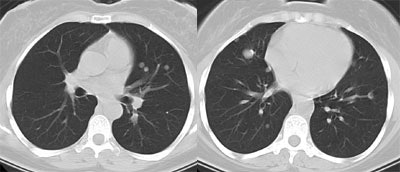

| Recurrent Hurthle cell carcinoma: The patient had a history of Hurthle cell carcinoma of the thyroid. Pulmonary metastases are significantly more evident on the coincidence FDG PET examination (below left black arrows) when compared to the I131 scan (below right blue arrows). A CT scan confirmed the presence of pulmonary metastases (below). Note that a subtle bone metastasis to the high left parietal bone can be seen on I131 images. The FDG PET exam did not include this region. |